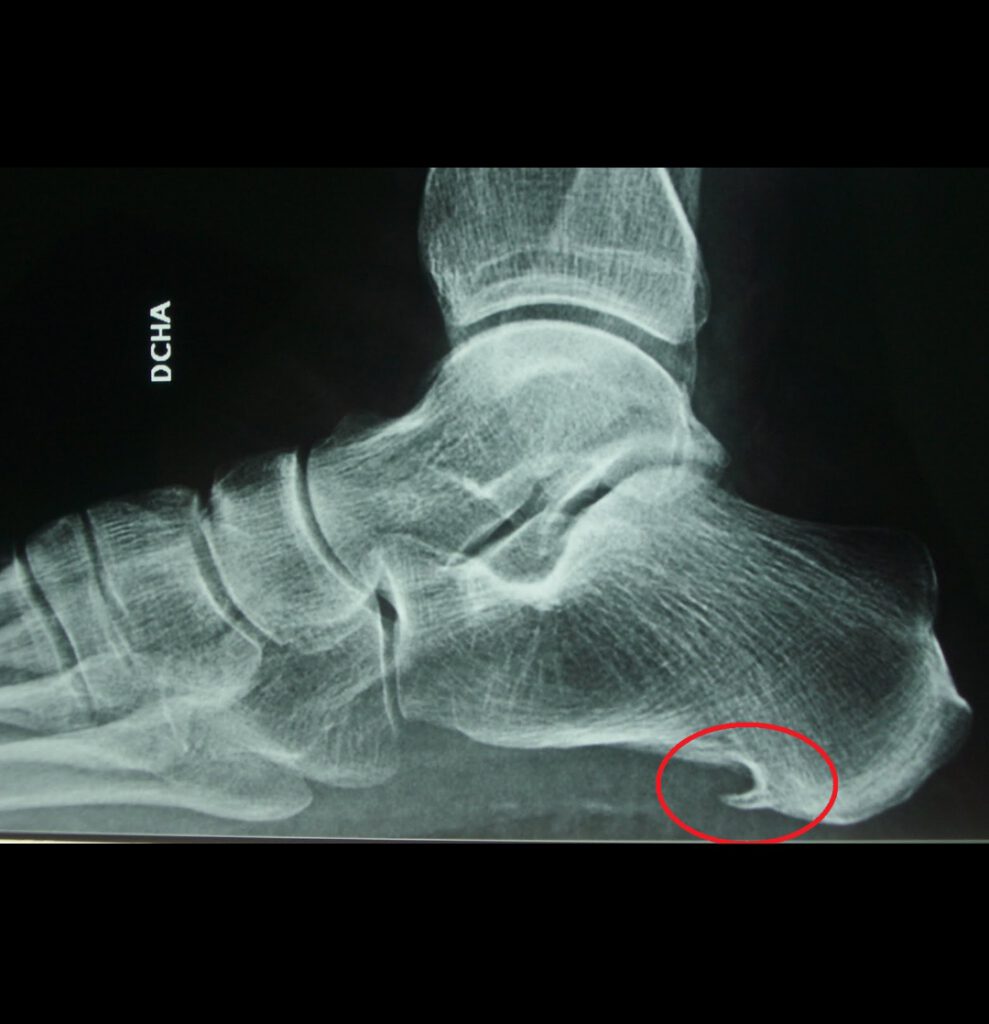

El espolón calcáneo es una excrecencia ósea que se forma en la parte inferior del hueso calcáneo. Suele estar asociado a una fascitis plantar crónica, siendo esta la verdadera responsable del dolor en la mayoría de los casos.

En una radiografía es frecuente observar el espolón, aunque no siempre es el tamaño del espolón lo que determina el dolor, sino la inflamación y degeneración de los tejidos que lo rodean.